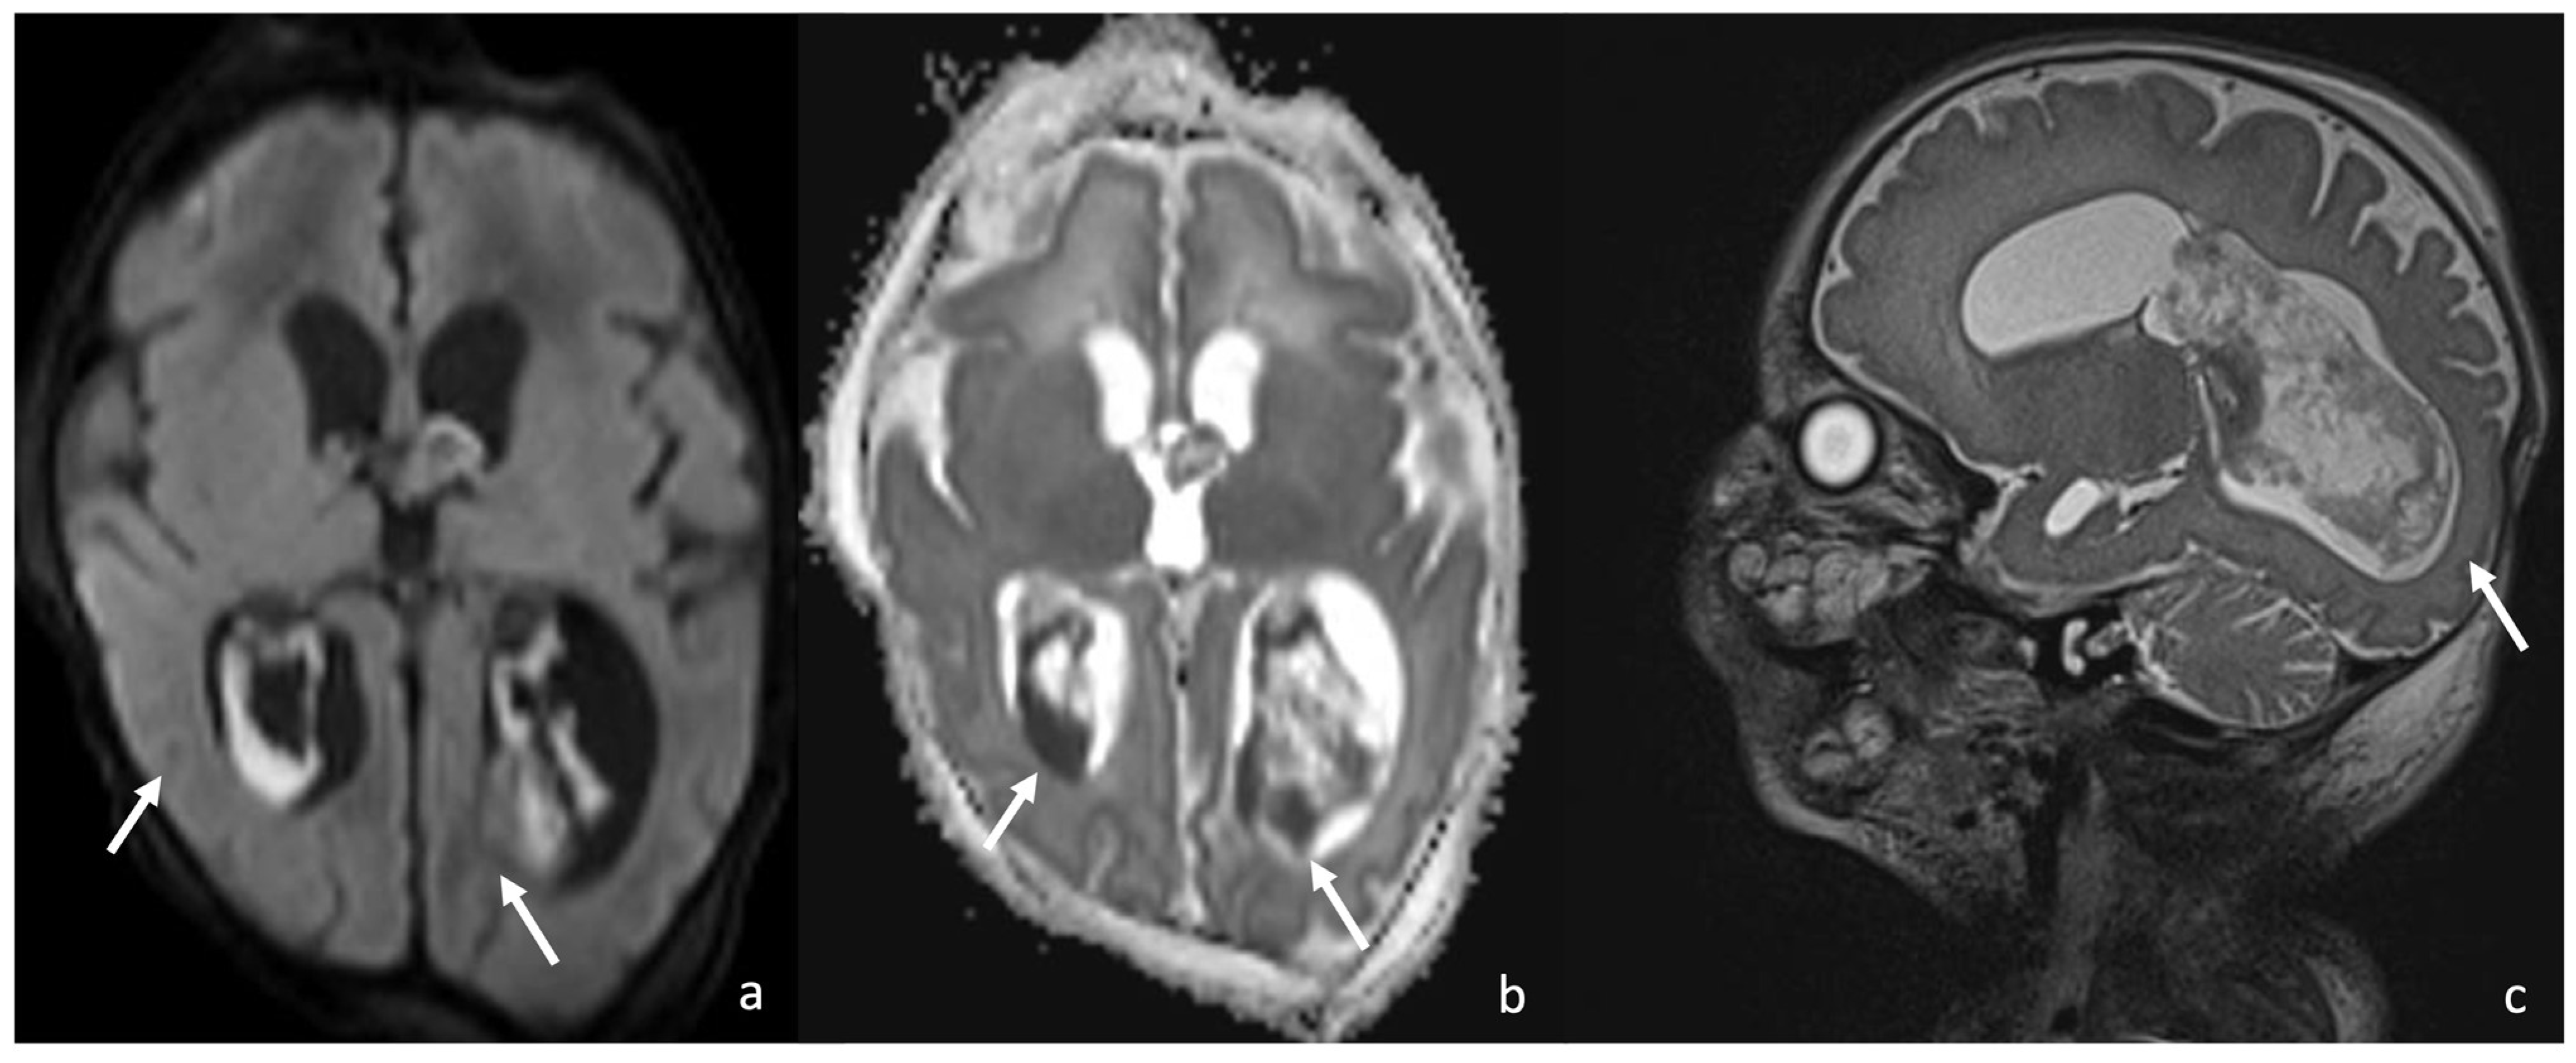

- Late capsule formation (weeks to months): The parenchymal abscess presents a necrotic core, appearing hypointense on T1WI and hyperintense on T2WI with diffusion restriction on DWI/ADC. The capsule is inhomogeneously thick, appearing thicker towards the cortex and thinner towards the ventricles, appears isointense on T1WI and hypointense on T2WI, and presents an intense enhancement. On the US, the abscess presents a well-defined hypoechoic core and a complete hyperechoic rim, pairing CT that shows a well-defined hypodense core and a complete peripheral enhancement.